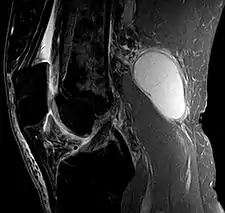

The synovial sac of the knee joint can, under certain circumstances, produce a posterior bulge, into the popliteal space, the space behind the knee. When this bulge becomes large enough, it becomes palpable and cystic. Most Baker's cysts maintain this direct communication with the synovial cavity of the knee, but sometimes, the new cyst pinches off. A Baker's cyst can rupture and produce acute pain behind the knee and in the calf and swelling of the calf muscles.

Diagnosis is by examination. A Baker's cyst is easier to see from behind with the patient standing with knees fully extended. It is most easily palpated (felt) with the knee partially flexed. Diagnosis is confirmed by ultrasonography, although if needed and there is no suspicion of a popliteal artery aneurysm then aspiration of synovial fluid from the cyst may be undertaken with care. An MRI image can reveal presence of a Baker's cyst.